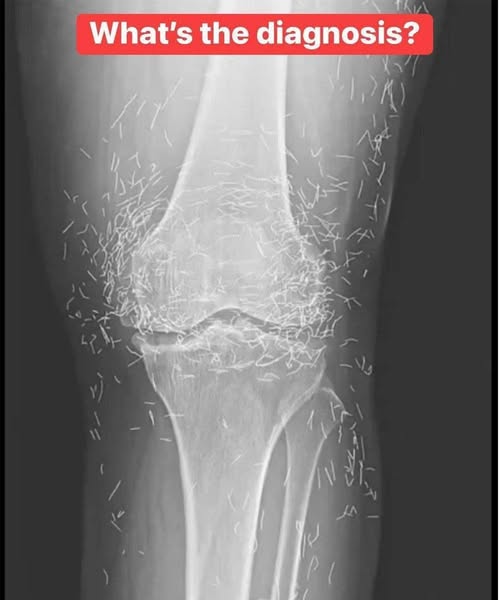

When doctors examined the X-ray of a 65-year-old woman in South Korea with severe knee pain, they didn’t just see signs of osteoarthritis.

They saw something unexpected: hundreds of tiny metallic fragments embedded in her knee joints.

In 2018, South Korean doctors published a case study about a woman with advanced osteoarthritis who had received repeated gold acupuncture treatments over 30 years.

She had been receiving gold wire implants in her knees and lower back for chronic pain

The “needles” were actually microscopic gold threads, about 0.2 mm thick and 3–5 mm long

Over decades, she received dozens of implants — not “hundreds” in a single session

When her knee pain worsened, an X-ray revealed numerous tiny metallic specks — the remnants of long-term gold implantation.